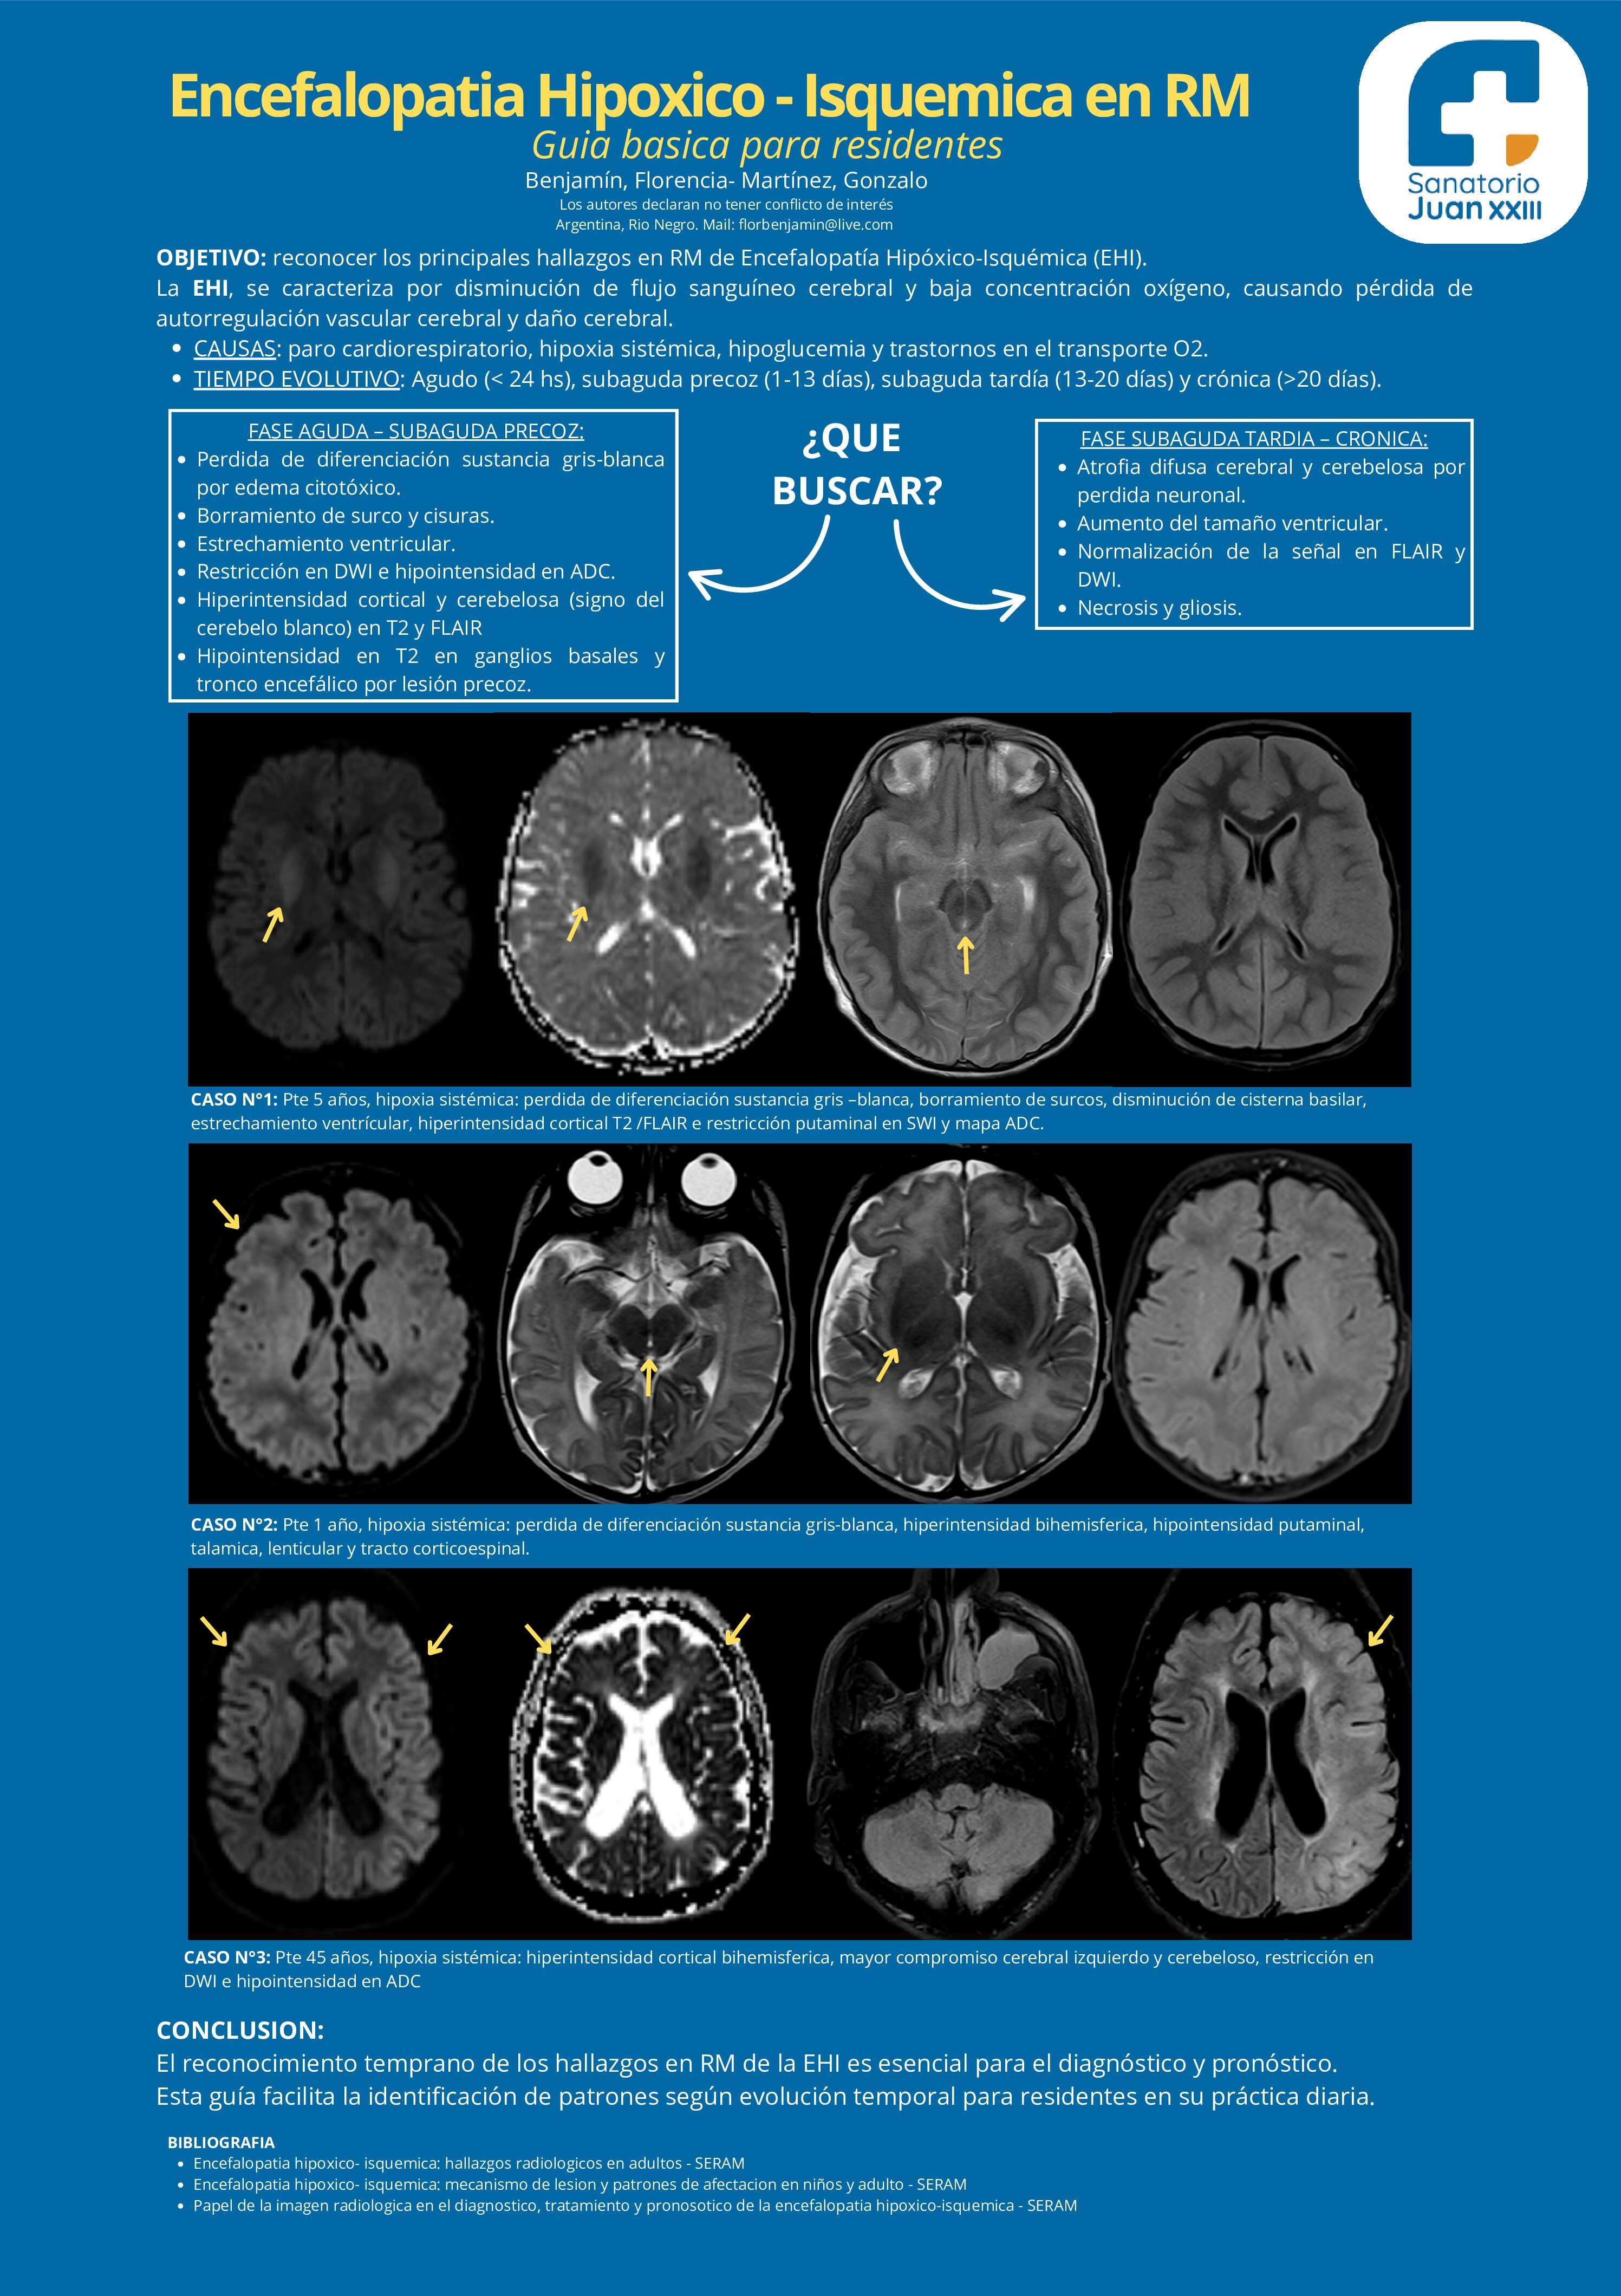

Encefalopatia Hipoxico-IsquemicaenRM

07/07/2025